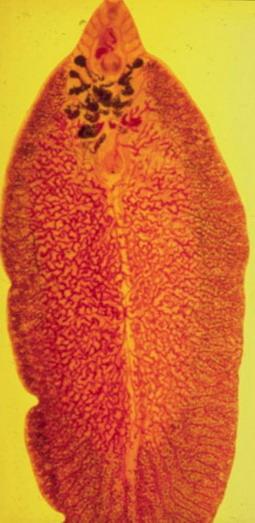

Паразит листоподібною форми, довжиною 15-50 мм Дорослі гельмінти паразитують у тонких кишках людини, свині, собаки. З фекаліями хворих фасциолопсидозом виділяються яйця паразита. При попаданні яєць у воду через 2-3 тижні у них формуються зародки, які виходять назовні і проникають у равликів. У равликів відбувається розмноження личинок гельмінта, що закінчується виходом у воду личинок - церкариев. Церкарий інцистуються на воді та рослинах. Зараження фасциолопсидозом відбувається при проковтуванні личинок з водою і при вживанні в їжу в сирому вигляді водяних горіхів і бульб ряду водяних рослин. Фасциолопсидоз поширений в Китаї, Таїланді, Індії, на Філіппінських островах.